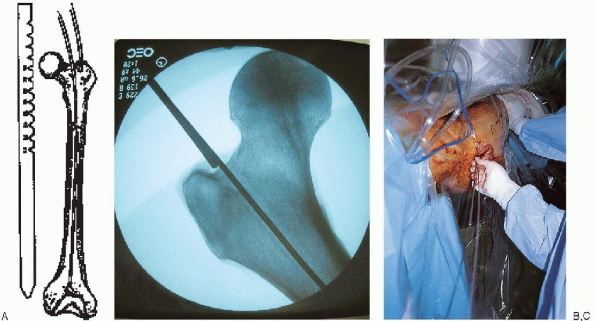

FIGURE 36-18. A: Determination of proper nail length using a radiolucent ruler or two identical length guide wires. B and C:

A second guide wire is overlapped with the portion of the reduction guide wire extending proximally from the femoral entry portal; this distance is subtracted from total guide wire length to determine nail length. |

of proper nail length can be made from preoperative planning and

verified using two identicallength guide wires or a radiolucent ruler.

In the guide wire method, a second guide wire is overlapped with the

portion of the reduction guide wire extending proximally from the

femoral entry portal (Fig. 36-18); this distance is subtracted from total guide wire length to determine nail length.

Alternatively, the radiolucent ruler is positioned over the anterior

femur, and image intensification used to make a direct reading of the

distance from the entry portal to the desired distal nail tip.